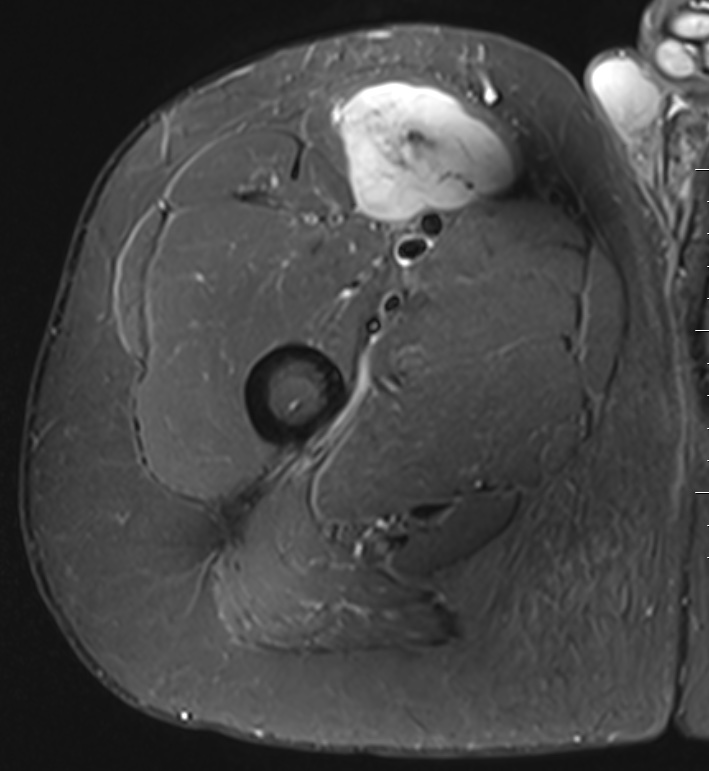

Liposarcoma

MRI

Deep to fascia / heterogenous

Liposarcoma anterior thigh